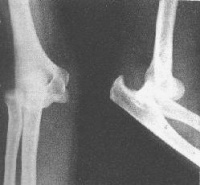

肱骨远端与桡、尺骨近端的关节对位关系发生分离。以肱骨远端为标准点,桡尺骨近端向后上方移位为后脱位,向前下方移位为前脱位,向侧方移位为侧方脱位。以肘关节后脱位为最常见。

3.X线检查 肘关节正侧位片可显示脱位类型、合并骨折情况,并与髁上骨折相区别。